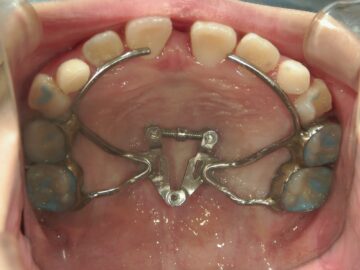

上顎の骨には繋ぎ目が存在しており、そこで左右二つの骨に分かれています。急速拡大装置を上顎に固定して装置の中央にあるネジを回すことで繋ぎ目を広げ、徐々に上顎の骨の変えていきます。そうすることで、顎の骨が正しい形に成長していくよう促され、永久歯を正しい位置で生えるように誘導できます。

急速拡大装置で上顎の拡大が進むと、下顎の骨も調整する必要が出てきます。その際に使う装置がリンガルアーチです。下顎の骨は上顎の骨と作りが違います。下顎はひとつの骨で構成されているので、上顎と同じように拡大させることができません。内側に傾いている歯を起こすようにして歯列部分だけを拡げていきます。この装置も固定式の装置となっており、歯の裏側に装着しますので目立たない見た目となっています。